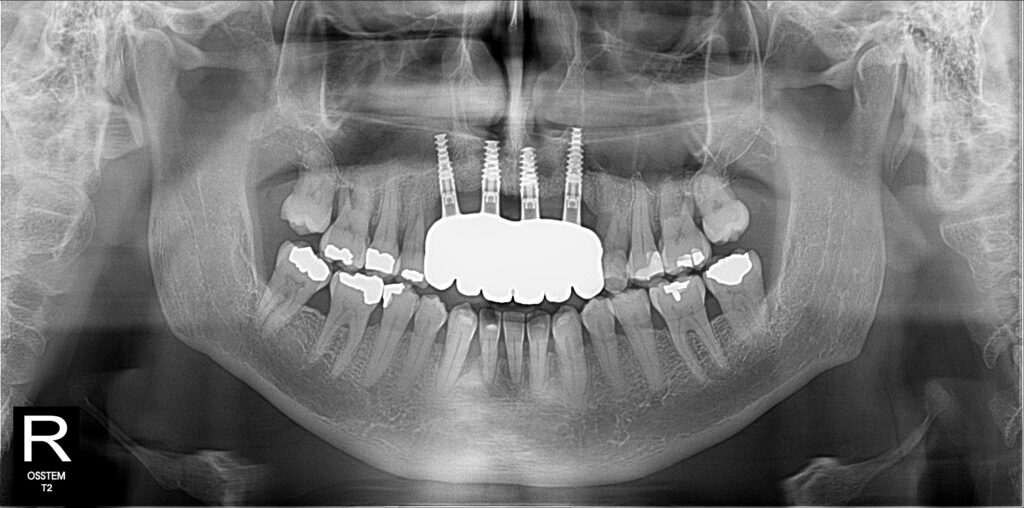

A selection of partial arch fixed implant bridge patients

Oral Surgeons – Dr Han Choi, Dr Sam Goldsmith, Dr Rajiv Rajpal NSOMS

Prosthodontist – Dr Alan Payne NSOMS/Northland Prosthodontics

Dental technicians – Hosaka Takashi, DT Denture Design, Auckland, CJ Park, Project Dentistry, Auckland and Osteon Medical, Melbourne, Australia.